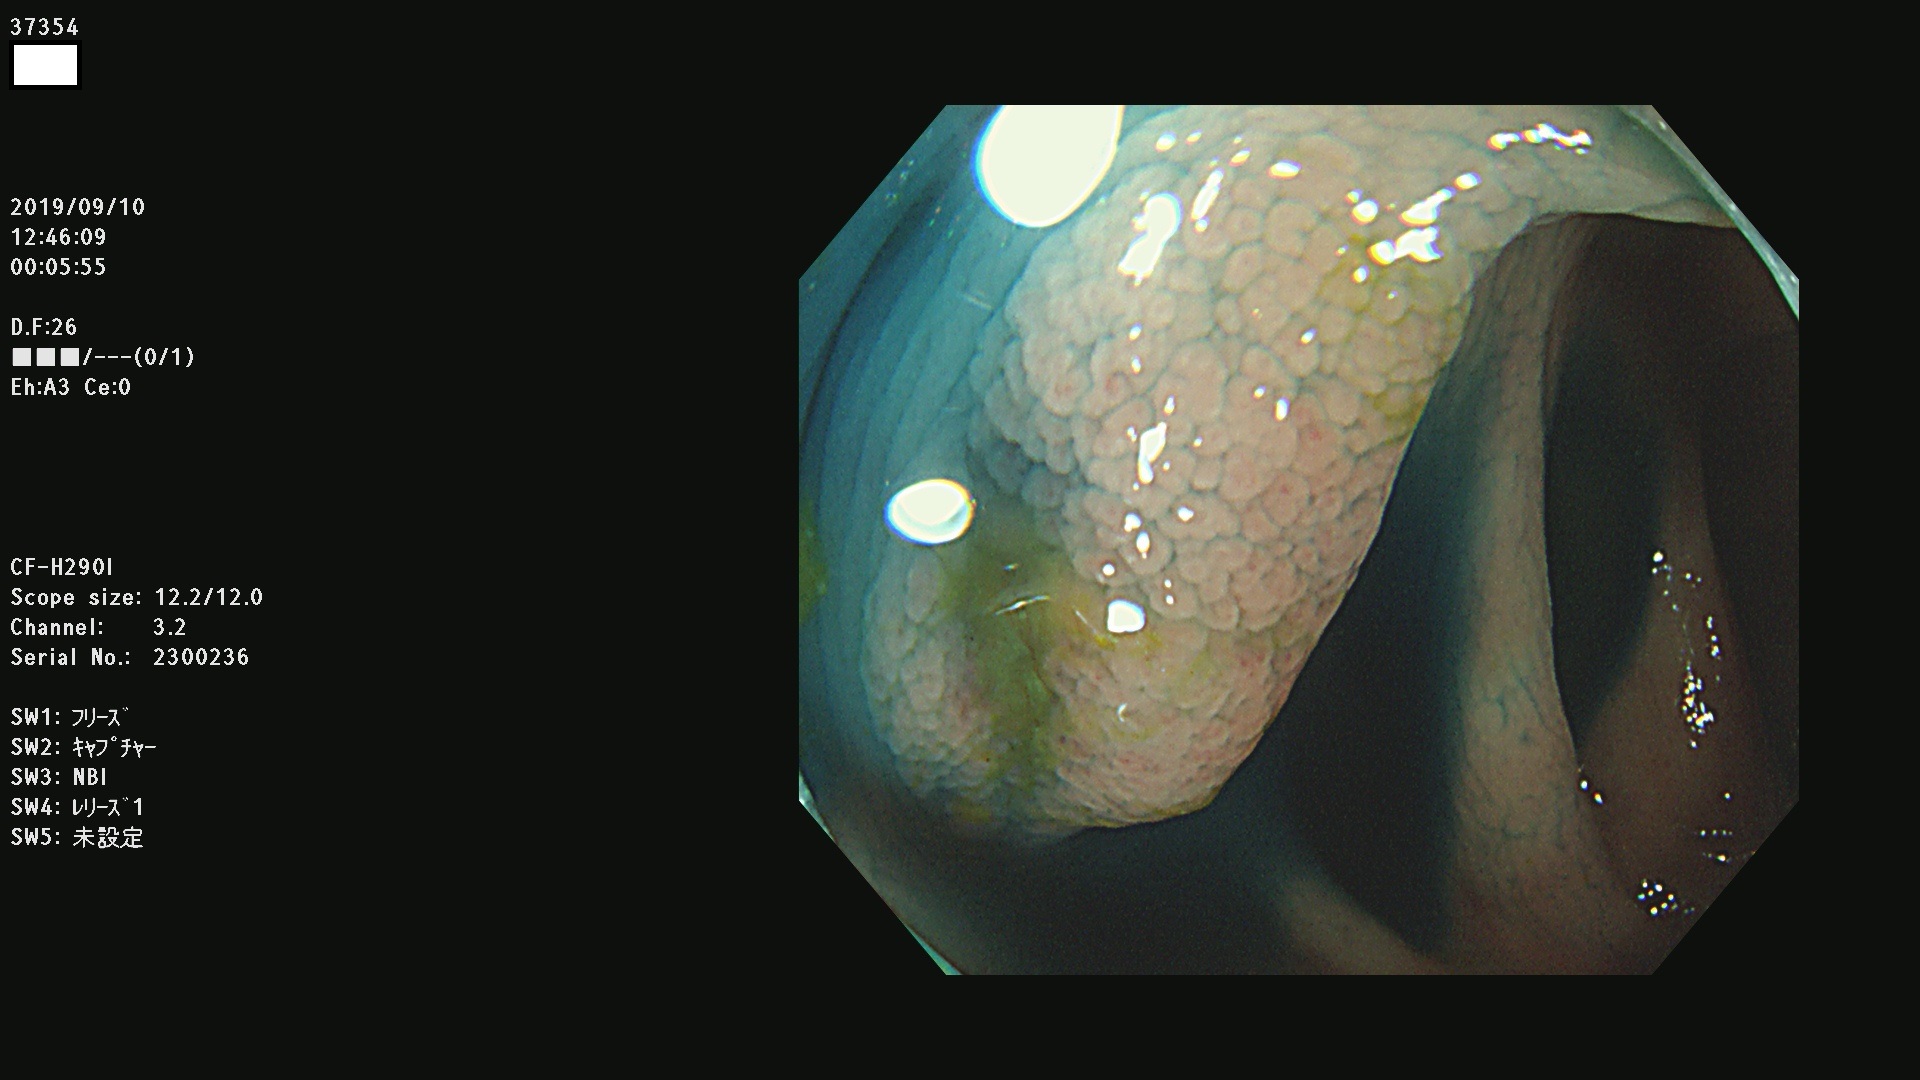

37300(SSAPのみ) 37301 37303 37304 37306 37307 37308 37309 37312 37313 37315(SSAPのみ) 37316 37317(SSAPのみ) 37319 37321(SSAPのみ) 37322 37323 37324 37325 37326 37328(SSAPのみ) 37329 37330 37331 37332(SSAPのみ) 37333 37334 37336 37337 37338 37340 37342 37343(SSAPのみ) 37344 37345 37346 37347 37348 37352(SSAPのみ) 37353 37354 37355 37356 37358 37360 37361(SSAPのみ) 37362 37363 37366 37367 37369 37370 37371 37372(SSAPのみ) 37375 37376 37377 37380 37381(SSAPのみ) 37382 37383 37384 37385(SSAPのみ) 37386 37387 37388 37389 37390 37392(SSAPのみ) 37393 37394 37395 37396(SSAPのみ) 37397 37398(SSAPのみ) 37399

発見困難で危険性の高い平坦型病変(上記100名より抽出) )